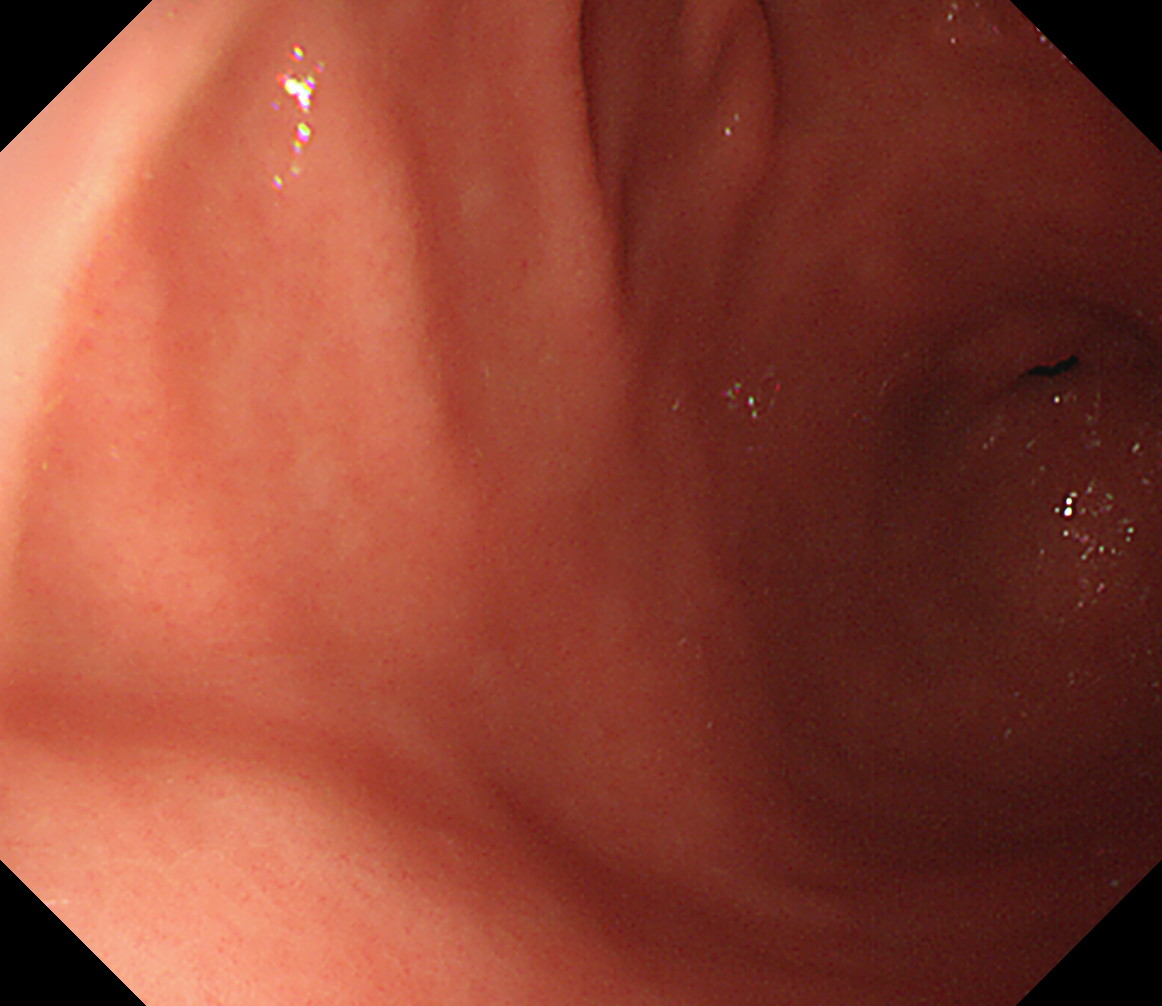

1 食道中部 門歯から約25cm 中部食道

2 食道下部 門歯から約35cm 食道下部